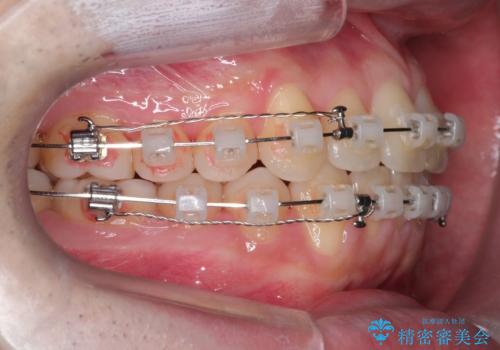

【クリア装置】前歯の凸凹を綺麗にしたい

- 前歯の凸凹を主訴に来院されました。

マウスピース矯正も適応でしたが、ワイヤー矯正を希望され治療を行なっております

治療期間も短く大変満足していただきました。